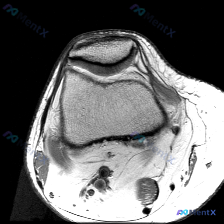

刚整理了一个很有代表性的读片病例,临床怀疑膝关节软骨异常,只提供了一张膝关节MRI轴位T1加权图像,分享一下完整分析思路,大家一起讨论。 病例影像基本信息 本次仅提供单张膝关节MRI轴位T1加权图像,影像学观察结果如下: 1. 骨骼结构:髌骨、股骨髁骨皮质连续,未见明显骨折线,骨髓信号符合正常T1加...